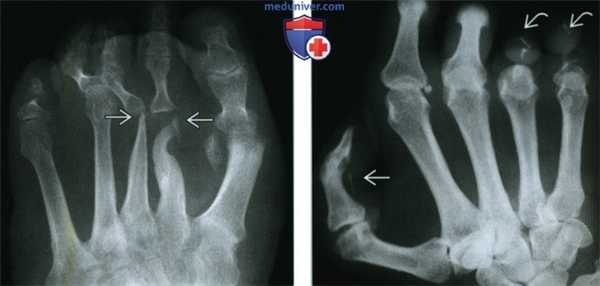

(Слева) Рентгенография в ПЗ проекции, выполненная у пациента с лепрой: разрушение плюсневых костей выражено значительно больше, чем дистальных фаланг. Этот случай не соответствует другим причинам акроостеолизиса, делая лепру наиболее вероятным диагнозом, что и было доказано.

(Справа) Рентгенография в ЗП проекции: выраженный акроостеолизис, большая часть фаланг разрушена. Кроме того, отмечается линейная кальцификация в зоне нерва пальца. Эта комбинация признаков патогномонична для лепры.